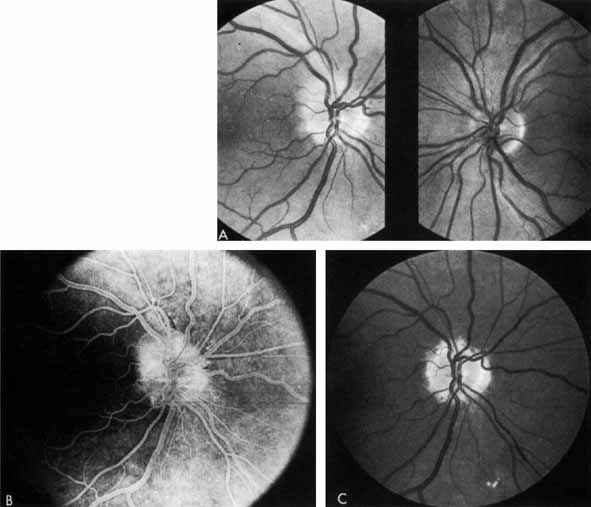

OPTIC NEUROPATHY

As demonstrated by increased latency and decreased amplitude of the visual evoked potential, many patients with diabetes without retinopathy have subclinical optic neuropathy.269,270 In addition, patients with diabetes can develop two types of acute optic neuropathy. The first, anterior ischemic optic neuropathy (AION) is identical to that seen in patients without diabetes. The patients report a sudden decrease in visual acuity or a sudden visual field loss.271–273 The main ocular finding is a “pale swelling” of the optic nerve head with, considering the degree of disc edema, very few hemorrhages (Fig. 27). On fluorescein angiography segmental nonfilling or slow filling is seen (Fig. 27). An afferent pupillary defect (Marcus Gunn) is nearly always present. Visual fields commonly show altitudinal or nerve fiber bundle defects. The disc progresses to optic atrophy (Fig. 27), and improvement in visual function is rare.

Fig. 27 A. Right eye: ischemic optic neuritis. Note pale swelling of optic disc and blurring of disc margins. Left eye: normal disc. B. Fluorescein angiogram. Note poor filling on disc inferotemporally as compared with the rest of the disc. C. Right eye 6 months after optic neuritis. Note slight pallor.